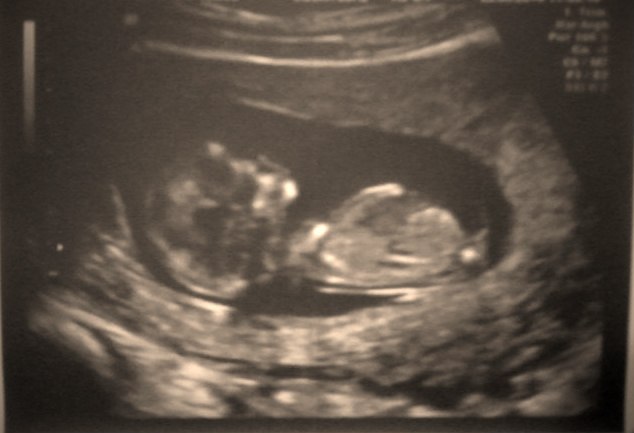

Первый скрининг!!!!!!!!!!!!!!!!

Я заплакала, когда увидела, как мой маленький там плавает! И дергается там и ручки к голове прикладывает! Врач мне аж замечание сделала, что мешаю ей работать. А я остановится не могла! Первый волшебный ребеночек!

КТР плода: 57 мм

БПР плода: 20 мм

ЧСС: 152 уд/мин

ТВП: 1,1 мм

ЖМ: д. 7 мм

В норме эти цифры?